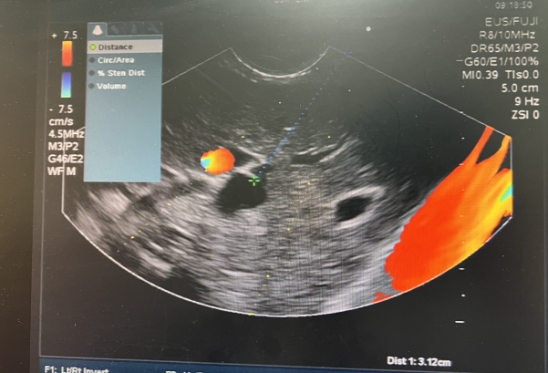

超声内镜定位胆内胆管

左图:超声内镜成功穿刺胆管并顺行留置导丝

右图:成功留置胆道支架